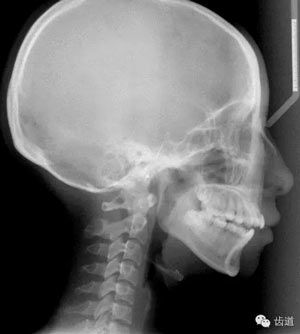

Measurements | Normal | Pre-T |

SNA | 81.69±2.54 | 73.6 |

SNB | 78.94±2.19 | 67.8 |

ANB | 2.75±1.16 | 5.8 |

Facial angle | 85.10±5.80 | 79.2 |

U1-SN | 105.7±6.3 | 98.5 |

L1-MP | 96.3±5.80 | 93.3 |

U1-L1 | 129.70±9.01 | 118.9 |

U1-NA | 5.56±3.6 | 4.8 |

U1-Nao | 23.26±6.17 | 24.9 |

L1-NB | 5.76±2.29 | 6.8 |

L1-Nbo | 27.38±4.74 | 30.5 |

OP-FH | 9.50±4.00 | 21.1 |

FMA | 28.80±5.20 | 37.7 |

IMPA | 96.3±5.80 | 93.3 |

FMIA | 54.6±6.5 | 49.0 |

下頜后縮為主要特征的骨性II類,高角,前牙開(kāi)合,上前牙略唇傾,雙側(cè)下頜升支及髁狀突不對(duì)稱,右側(cè)較左側(cè)粗壯,左側(cè)髁狀突外斜面曾有吸收,但現(xiàn)骨白線與皮質(zhì)骨已比較連續(xù),上呼吸道正常。上

頜第三磨牙牙冠較小。